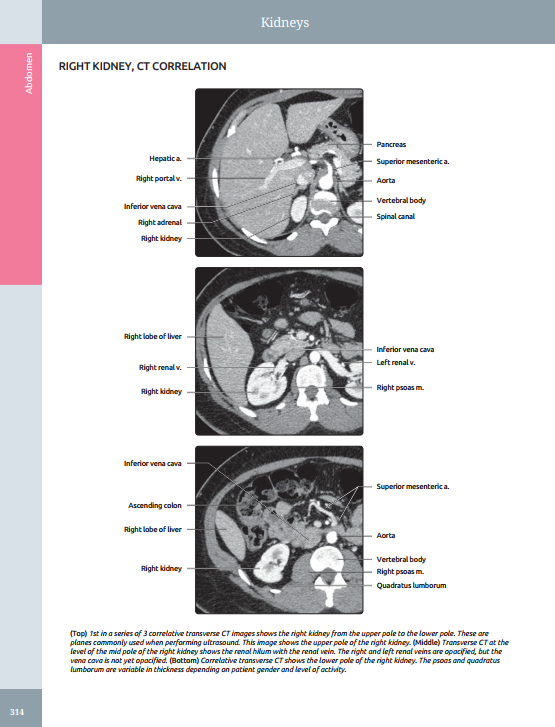

Presents richly labeled images with associated commentary as well as thumbnail scout images to show transducer placement

Features a robust collection of CT/MR correlations, highlighting the importance of multimodality imaging in modern clinical practice